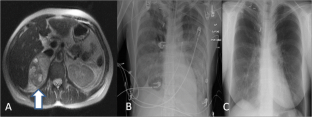

Fig. 1

Fig. 2